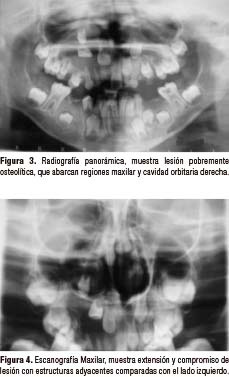

En la radiografía panorámica (Fig. 3) se observa amplia lesión con imagen pobremente radiolúcida unilocular con pequeñas radiopacidades en su interior proyectada en regiones que abarcan maxilar y cavidad orbitaria derecha aproximadamente 10 x 4 cm, con cortical parcialmente delimitada y bien definida, abarca en sentido transversal desde segmento radicular de pieza 21 hasta ápice de pieza 16, incluyendo ápices de piezas 51, 52, 53; y en sentido longitudinal desde cavidad orbitaria hasta 3mm superior al reborde alveolar. Se observa también dentro de la lesión imágenes radiopacas compatibles con piezas dentarias incluídas, correspondientes a piezas 13, 12, 11, las mismas que muestran desplazamientos en dirección cefálica. En la escanografía maxilar (Fig. 4) se puede observar la extensión y compromiso de la lesión con estructuras adyacentes comparadas con el lado izquierdo. La teleradiografía fue obtenida para observar la disposición y localización de las estructuras dentarias en relación a la lesión, mostrando más una vez desplazamiento de piezas dentarias comprometidas, pieza 13 con mínima cercanía a pared anterior de seno maxilar derecho (Fig. 5). En la radiografía oclusal se puede observar piezas 11 y 12 incluídas dentro de la lesión, flotando, condicionando desplazamiento de pieza 13 en dirección cefálica sin compromiso con seno maxilar derecho (Fig. 6).